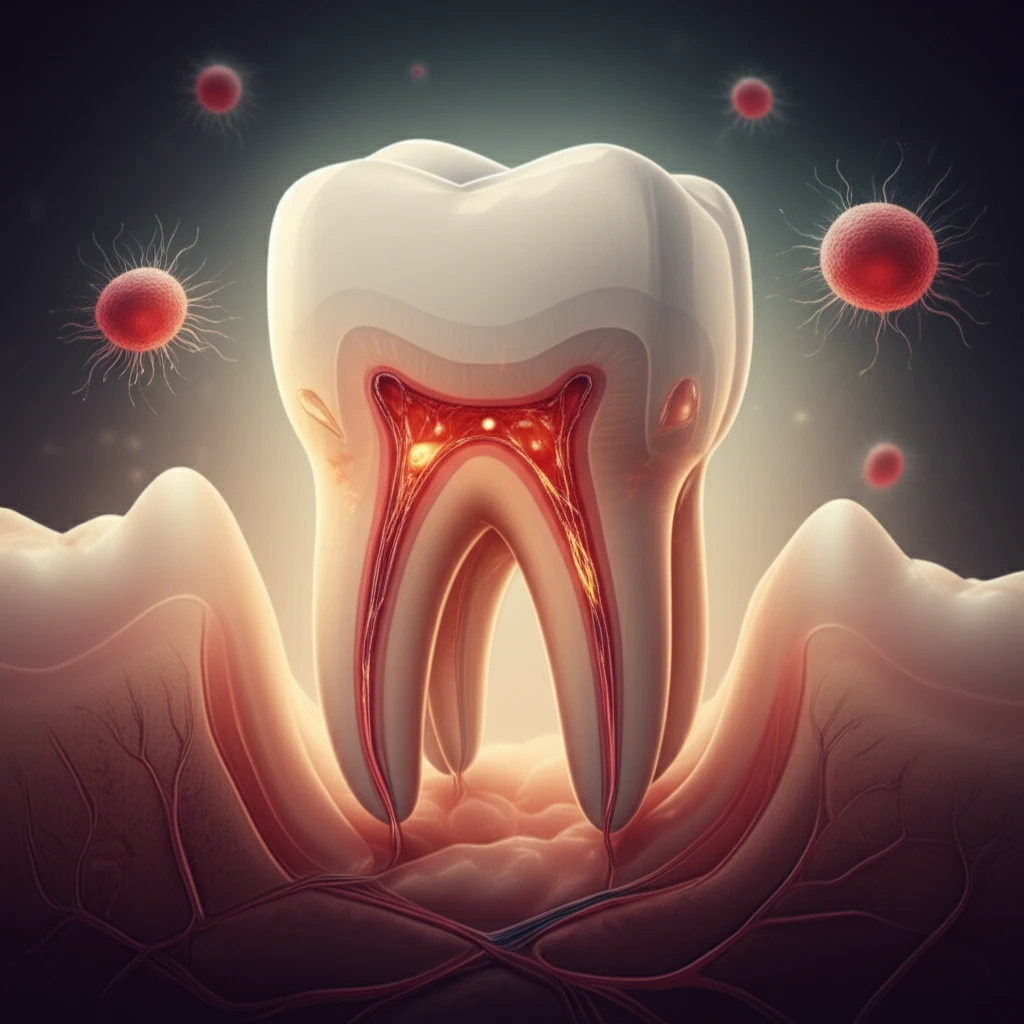

Root canals, dreaded by many, may be on the verge of a major upgrade. For years, traditional root canal therapy has focused on removing infected tissue and sealing the tooth, but a new approach is gaining momentum: regenerative endodontics. This innovative field aims to harness the body's natural healing abilities to regenerate damaged dental tissues.

Regenerative endodontic procedures (REPs) have demonstrated promising results, including resolution of disease symptoms and increased tooth survival. However, these procedures still face challenges, such as inconsistent root development and the formation of tissues that don't fully replicate the original pulp-dentin complex. New research is focusing on how to improve the predictability and effectiveness of REPs, particularly by understanding the role of stem cells.

Stem cells, with their remarkable ability to differentiate into various cell types, hold the key to true dental regeneration. Scientists are exploring how to optimize the environment within the tooth to encourage stem cells to rebuild damaged tissues, restore tooth vitality, and ultimately provide more natural and lasting solutions for dental health.

The apical papilla, located at the tip of developing teeth, is emerging as a crucial player in regenerative endodontics. This area is rich in mesenchymal stem cells, which can differentiate into various cell types needed for tooth repair and regeneration. Research suggests that the apical papilla can withstand infection and inflammation, making it a valuable resource for stem cell-based therapies.